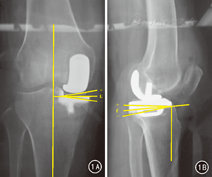

观察组除胫骨髓外定位器安放方法与对照组不同外,其余与对照组相同。不同点:术前在X线监视下标记踝关节标准正位上距骨中点,即踝关节中点,然后在踝关节中点与胫骨结节中内1/3处放置一枚克氏针,通过X线证实其通过膝关节中点和踝关节中点,沿金属导针在皮肤做标记。拍摄小腿全长侧位片,在侧位片上测量克氏针与机械轴的夹角,通过已知克氏针长度用三角函数计算出克氏针到机械轴的垂直距离。术中根据胫骨解剖轴体表标记线及计算结果精确安放胫骨髓外截骨定位器,使其矢状面上与体表标志线平行,冠状面上与胫骨机械轴平行,从而保证胫骨髓外定位杆在正侧位上与胫骨解剖轴都是平行的。完成胫骨截骨。术前体表标记胫骨解剖轴及测量计算均由同一组医生完成,采用相同定位标准及测量软件。

两组术后所有患者无切口感染、脂肪栓塞或下肢深静脉血栓形成。术后第3天复查膝关节正侧位X线片,测量观察组E角绝对值1.25°±0.52°、F角绝对值1.08°±0.51°,对照组E角绝对值4.02°±0.53°、F角绝对值3.88°±0.54°,差异均有统计学意义(t=13.451、13.592,P值均<0.01)。两组均无力线不良。典型病例见图2。

本方法通过术前精确体表标记胫骨解剖轴辅助进行UKA手术,可以实现术中精确安放胫骨髓外定位器,从而对内侧胫骨平台行精确截骨。在正常下肢力线中,股骨头中心、膝关节中心及踝关节中心位于一条直线上,为下肢的机械轴,而胫骨机械轴从膝关节中心到踝关节中心,也是胫骨的解剖轴[19]。对于适合行内侧单髁置换手术的膝内侧间室骨关节炎的患者,内翻畸形较轻(<15°),一般在膝关节屈曲至90°小腿自然下垂的状态下内翻畸形基本纠正;这是由于膝关节前内侧间室骨关节炎患者其胫骨平台后方软骨是完整的,前叉韧带功能良好,在膝关节屈曲后,股骨内髁移至胫骨平台后方正常软骨后,内翻畸形也自行矫正。因此,我们通过术前精确体表标记胫骨解剖轴指导术中精确安放胫骨髓外定位器,在术中对胫骨内侧平台垂直截骨只要在膝关节屈曲90°将锯片与骨髓外定位器和克氏针在矢状面上相平行即基本指向了股骨头中心,很好地解决了因胫骨旋转及股骨头指向困难所造成的误差。通过术前测量侧位片上克氏针与机械轴的夹角,通过已知克氏针长度,用三角函数计算前后位移值,术中将胫骨髓外定位器在侧位上与体表标记线平行,然后根据术前计算的位移值调整胫骨髓外定位杆,使之与胫骨机械平行,这样胫骨内侧平台水平截骨也更加准确。同时,通过胫骨解剖轴的体表划线,我们在置入股骨髓内定位杆时保持与该线呈6°左右内翻(股骨解剖轴与下肢机械轴约呈6°夹角)即可轻松插入。在进行此部操作时,注意由于已经进行过内侧平台截骨,膝关节呈内翻位,需一名助手帮助纠正膝内翻,即做膝外翻应力保持正常内侧副韧带张力即可。